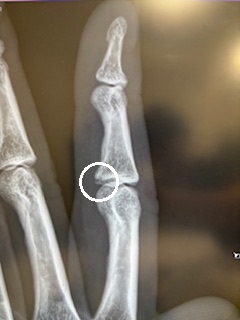

さらに拡大👇

(ほんの少し隙間が開いているの分かりますか?そこです)